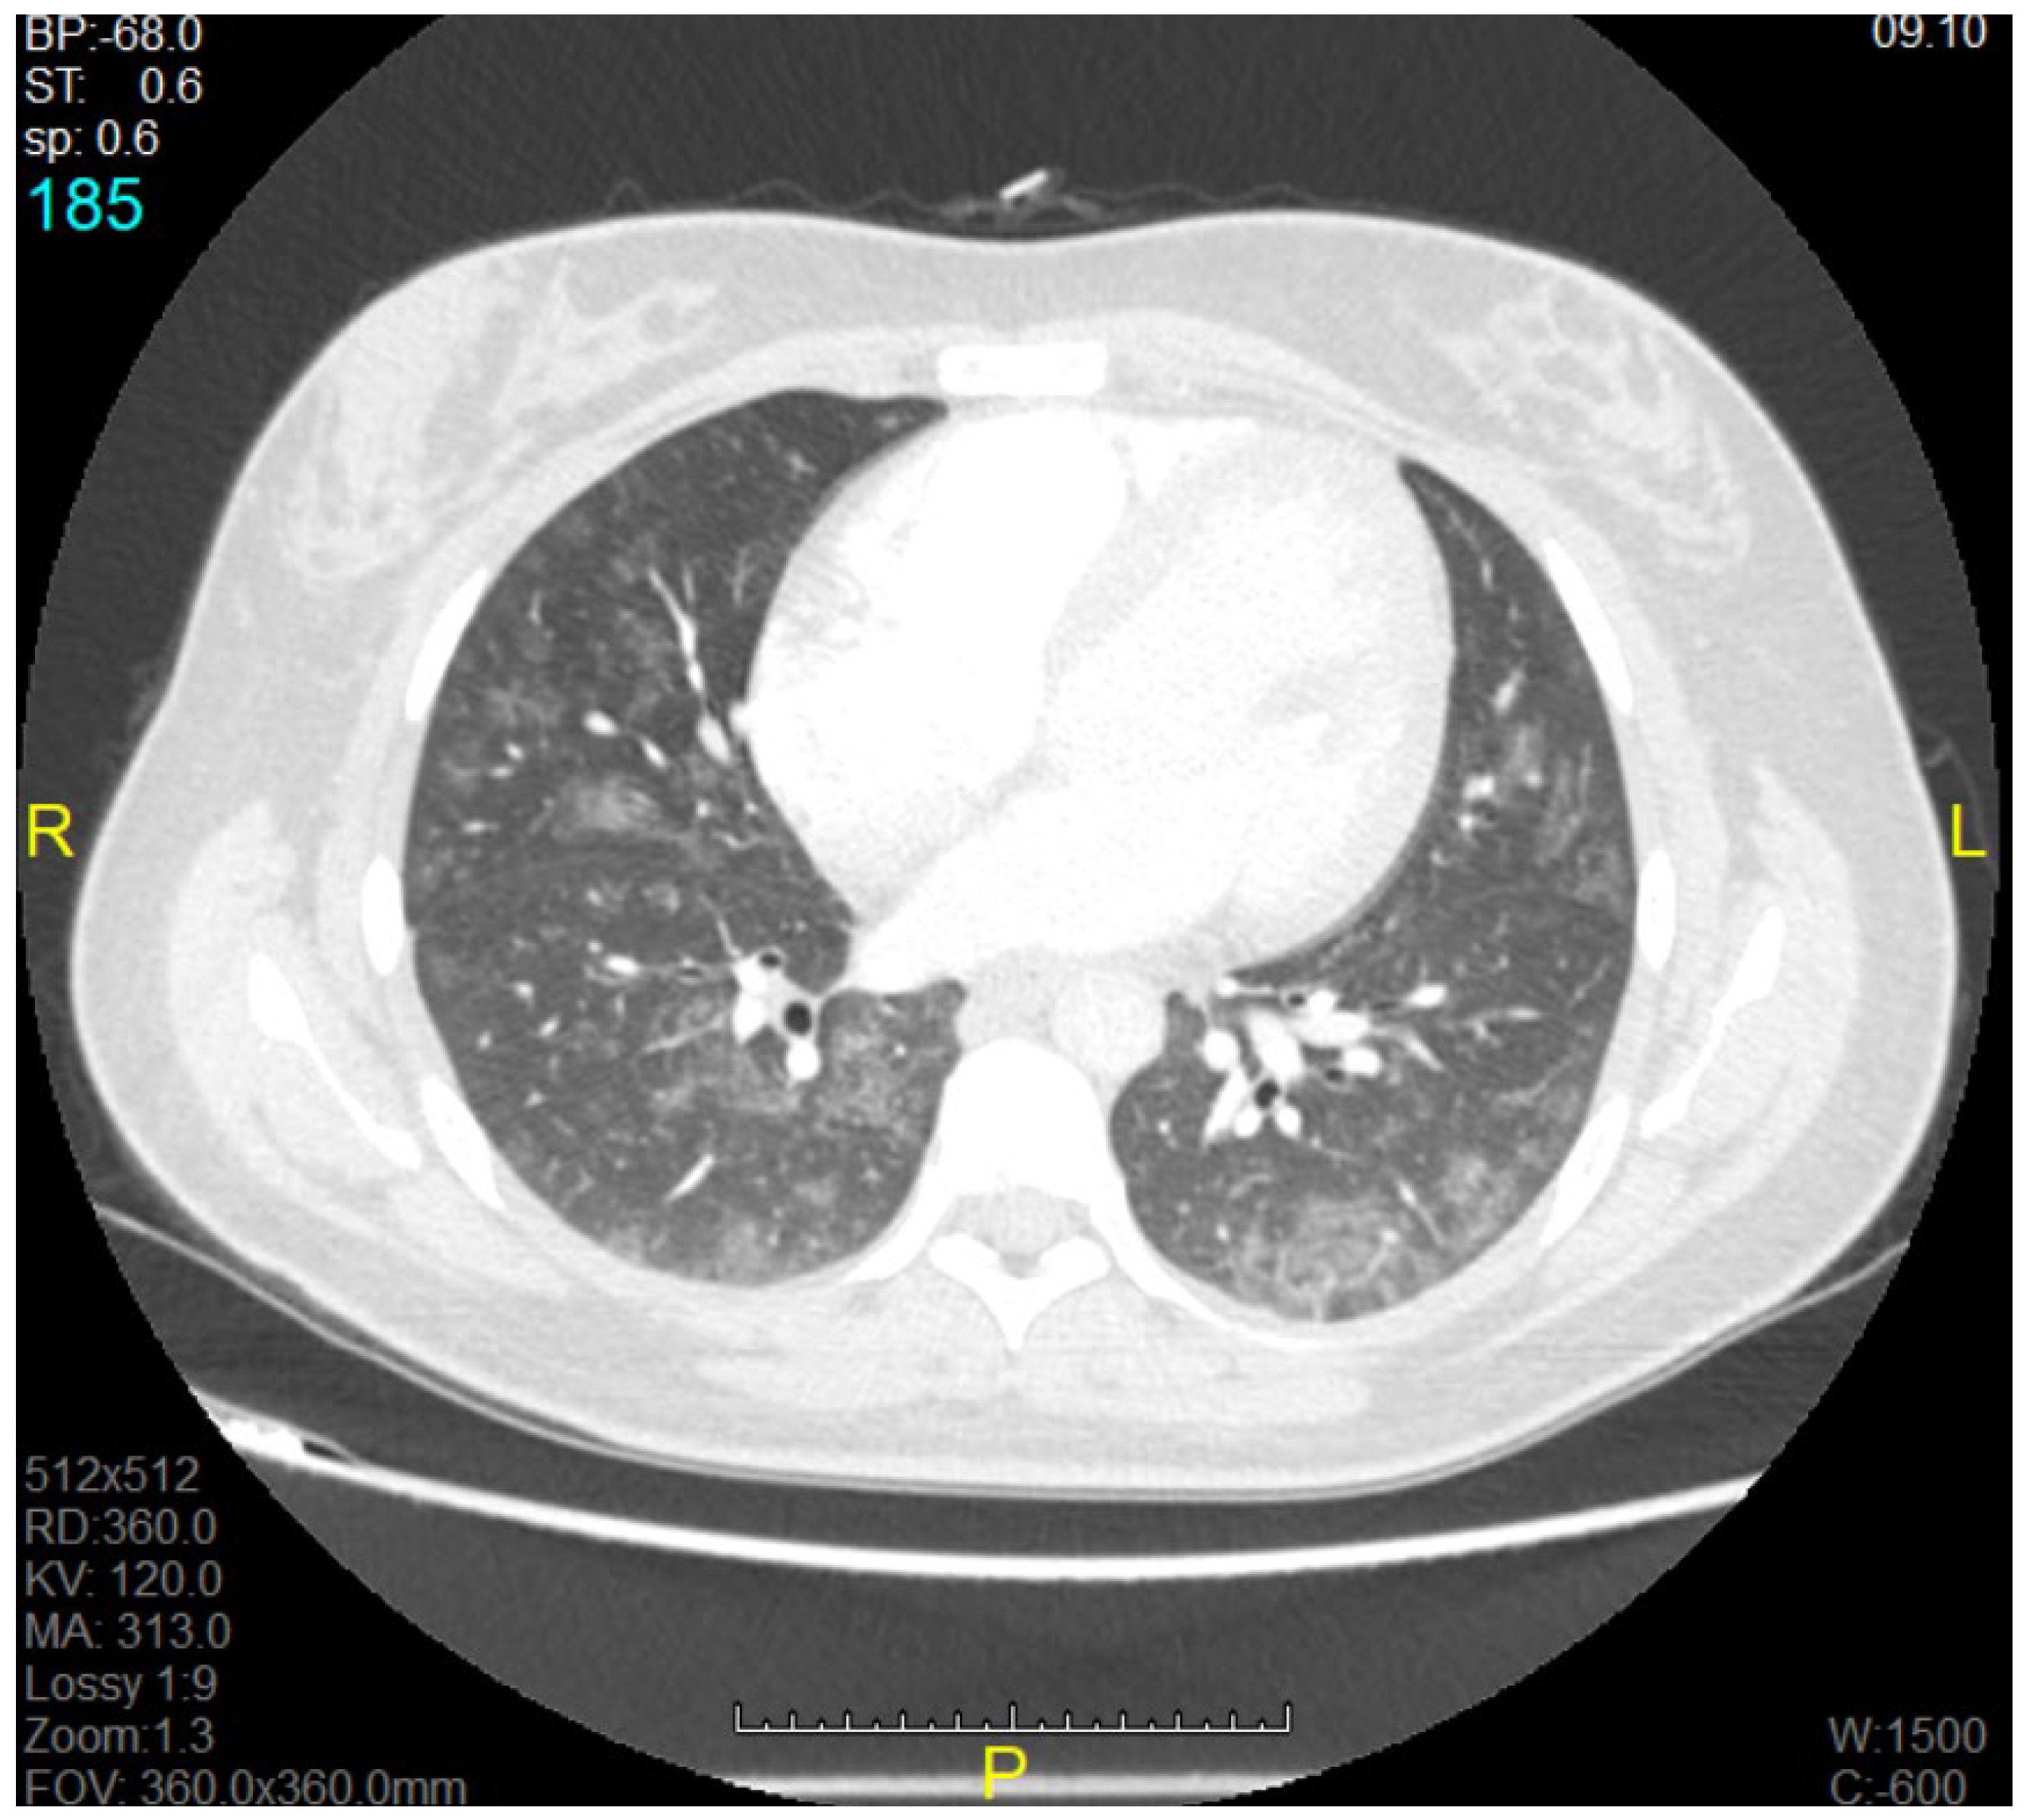

The mean ± SD of the gestational age of all the born babies in this study was 31.43 ± 4.35. The main clinical symptoms on admission to the MICU were dyspnoea, coughing, and fever, which were present in 16 of 19 patients (84.21%). All 19 patients had bilateral infiltrates seen on a chest X-ray (CXR) or computerised tomography (CT) scan, along with a certain degree of ARDS. The most common findings during examination of the chest CT were bilateral diffuse ground glass-like infiltrations and pneumonic consolidation areas. On the chest X-rays, diffuse bilateral infiltration and increased opacity were seen (Figure 1 and Figure 2).

Figure 1. Computerised tomography (CT) image of a pregnant woman with acute respiratory distress syndrome (ARDS).